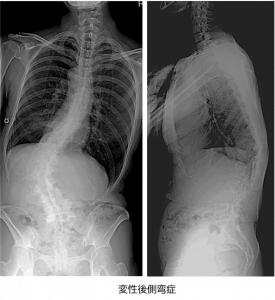

成人脊柱変形 変性後弯症・側弯症- 東京科学大学 整形外科。

脊柱変形側弯症と首下がり症疾患解説立川病院。

年を取って身体が曲がってきた。」なぜ側湾症になるのですか? - 湘南山手マッサージ治療院。